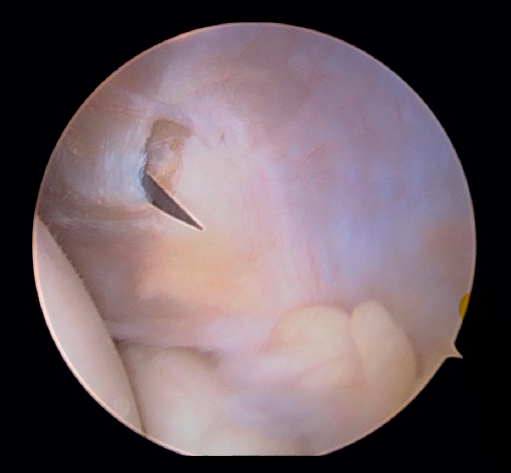

A continuación, se explora el compartimento anterior del codo en busca de sinovitis, lesiones condrales, cuerpos libres, plicas sinoviales o cualquier otra lesión, y se procede a su tratamiento mediante sinovectomía, desbridamiento, extracción o exéresis, respectivamente (Figura 6).

Figura 6. Compartimento anterior del codo, se aprecia la cabeza del radio y el cóndilo humeral junto con la cápsula articular lateral (paciente en decúbito lateral, codo derecho, visión desde el portal medial).